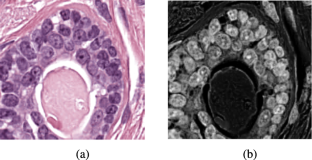

This paper addresses the task of nuclei segmentation in high-resolution histopathology images. We propose an automatic end-to-end deep neural network algorithm for segmentation of individual nuclei. A nucleus-boundary model is introduced to predict nuclei and their boundaries simultaneously using a fully convolutional neural network. Given a color-normalized image, the model directly outputs an estimated nuclei map and a boundary map. A simple, fast, and parameter-free post-processing procedure is performed on the estimated nuclei map to produce the final segmented nuclei. An overlapped patch extraction and assembling method is also designed for seamless prediction of nuclei in large whole-slide images. We also show the effectiveness of data augmentation methods for nuclei segmentation task. Our experiments showed our method outperforms prior state-of-the-art methods. Moreover, it is efficient that one 1000×1000 image can be segmented in less than 5 s. This makes it possible to precisely segment the whole-slide image in acceptable time. The source code is available at https://github.com/easycui/nuclei_segmentation.